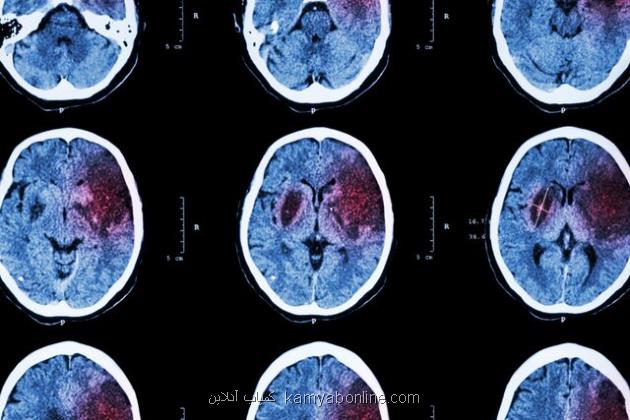

سکته مغزی زیر ذره بین پژوهشگران ایرانی

به گزارش کمیاب آنلاین به نقل از ایسنا، به نقل از بنیاد ملی علم ایران (INSF)، سکته مغزی یکی از بزرگترین مشکلات و بیماری هایی است که افراد جامعه را درگیر می کند و عوارض آن در طولانی مدت نمود پیدا می کند. محققان به دنبال راهکارهای برای کاهش عوارض آن هستند و بنیاد ملی علم ایران هم از طرح های در این حوزه حمایت می کند.

«بررسی آثار پیش درمانی بالقوه حاصل از تجویز miRNA-149-5p بر بهبود نقص های نورولوژیک در مدل سکته مغزی رت» عنوان طرحی است که در چارچوب رساله دکتری محمدرضا بیگدلی مسئول آن بوده و سمیرا وحیدی با حمایت بنیاد ملی علم ایران به پایان رسانده است. بیگدلی با مدرک دکتری تخصصی فیزیولوژی از دانشگاه تربیت مدرس در رابطه با این طرح توضیح داد: سکته مغزی بعنوان شایع ترین بیماری عروق مغزی و معضل اولیه سلامت عمومی شناخته می شود که با شیوع و مرگ ومیر بالا، شروع حاد، رشد سریع و نتایج شدید شناخته می شود و متأسفانه میزان بروز آن در حال افزایش می باشد.

وی افزود: سکته مغزی دومین عامل مرگ ومیر و علت اصلی ناتوانی جسمی است. هر سال تقریبا 15 میلیون نفر گرفتار سکته مغزی می شوند و حدود 5 میلیون نفر در سراسر دنیا فوت می کنند. با عنایت به صدمه شناسی زمینه ای، سکته مغزی امکان دارد بعنوان سکته مغزی ایسکمیک یا هموراژیک طبقه بندی شود.

این محقق و پژوهشگر خاطرنشان کرد: 85 درصد کل سکته ها، سکته مغزی ایسکمیک است، درحالی که سکته مغزی هموراژیک علت 15 درصد از سکته ها است. اخیراً، پیشرفت قابل ملاحظه ای در درک مکانیسم های پاتوفیزیولوژی سکته مغزی، بخصوص در سکته مغزی ایسکمیک صورت گرفته است.